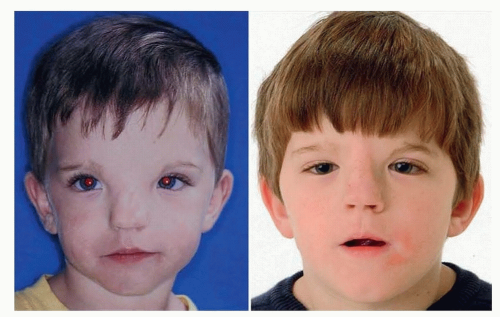

Ptosis Correction Surgery

This procedure addresses drooping upper eyelids caused by weakened eyelid muscles, improving both appearance and vision.Overview

Small incisions are made along the natural eyelid crease.The levator muscle (which lifts the eyelid) is tightened or reattached.

Excess skin may be removed, and sutures are used to secure the eyelid.

Pros:

Corrects droopy eyelids and improves field of visionLong-lasting results

Can be combined with upper blepharoplasty

Cons:

Swelling and bruising for 1–2 weeksRisk of asymmetry or overcorrection

Requires precise surgical technique for natural results

PTOSIS CORRECTION BEFORE & AFTER

Price: €1,500–€4,500